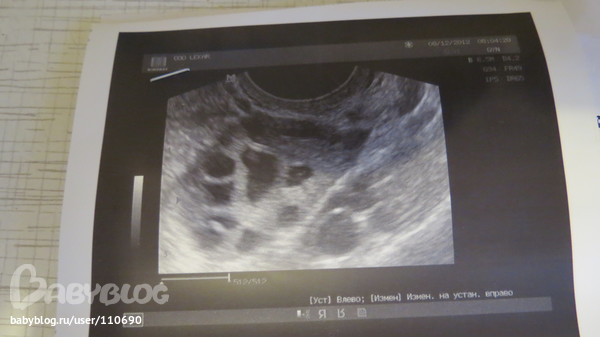

Ну вот и сходила на Фолликулометрию

Да видимо мне повезло, т.к она увидела фолликул и там жалостливо посмотрела, так сожалела,что наверно он не вылупится((( но я пойду на узи на 21 день,хочу посмотреть, что узи покажет. Теперь только узи, строго 3 раза в месяц.Тесты больше не покупаю.

Загиб матки ( Ретрофлексия ) Мой букет.